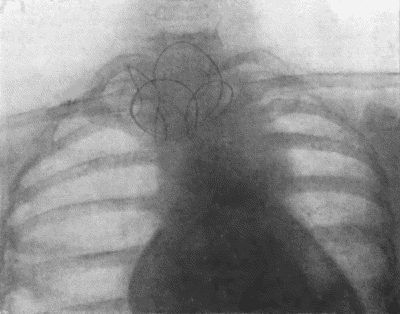

| 71. | Radiogram of Aneurysm of Aorta | 303 |

| 73. | Radiogram of Innominate Aneurysm after Treatment by Moore-Corradi method | 309 |